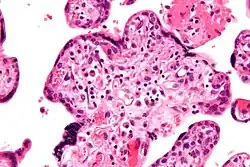

![]() Micrografía de vilitis de etiología desconocida. Tinción H&E. | ||

Histomorfológicamente, la VUE se caracteriza por un infiltrado linfocitario de las vellosidades coriónicas sin una causa demostrable. Las células plasmáticas deben estar ausentes; la presencia de células plasmáticas sugiere una etiología infecciosa, por ejemplo, infección por CMV.

Villitis crónica de bajo grado -

Villitis crónica de alto grado